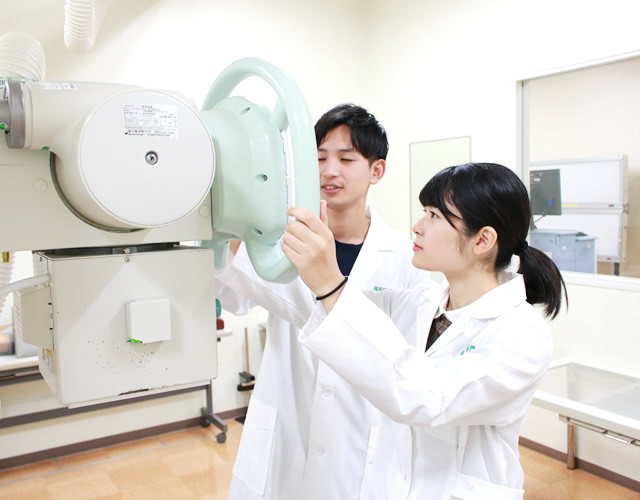

臨床実習

大学病院や総合病院で2年次に5週間、3年次に5週間行います。学校で学んだ知識や技術を、現場で体験する機会です。また、診療放射線技師としての心構えや病院の雰囲気を直接肌で感じ、卒業後の技術修得に役立てることができます。

2年次

主にX線撮影、CT検査、MRI検査を学びます。解剖学的知識と結び合わせ、最適な撮影方法を修得します。

MRIは磁場を利用した診断装置で、体の任意の断面画像を撮影することが可能です。現代医療においては、欠かすことの出来ない高度医療機器のひとつになっています。今回の実習では臨床の場を想定してMRIの撮影を学生自ら行いました。学生は装置の準備や撮影条件の設定、撮影部位の位置合わせなどに関して担当教員より指導を受けながら撮影を進めていきます。また、患者さんへの検査の説明や検査機器への誘導などの接遇も実習課題となっています。

患者さん役(学生)を撮影室に呼び入れる前に装置のセッティングを行っています。女子3名で準備は完了しました。